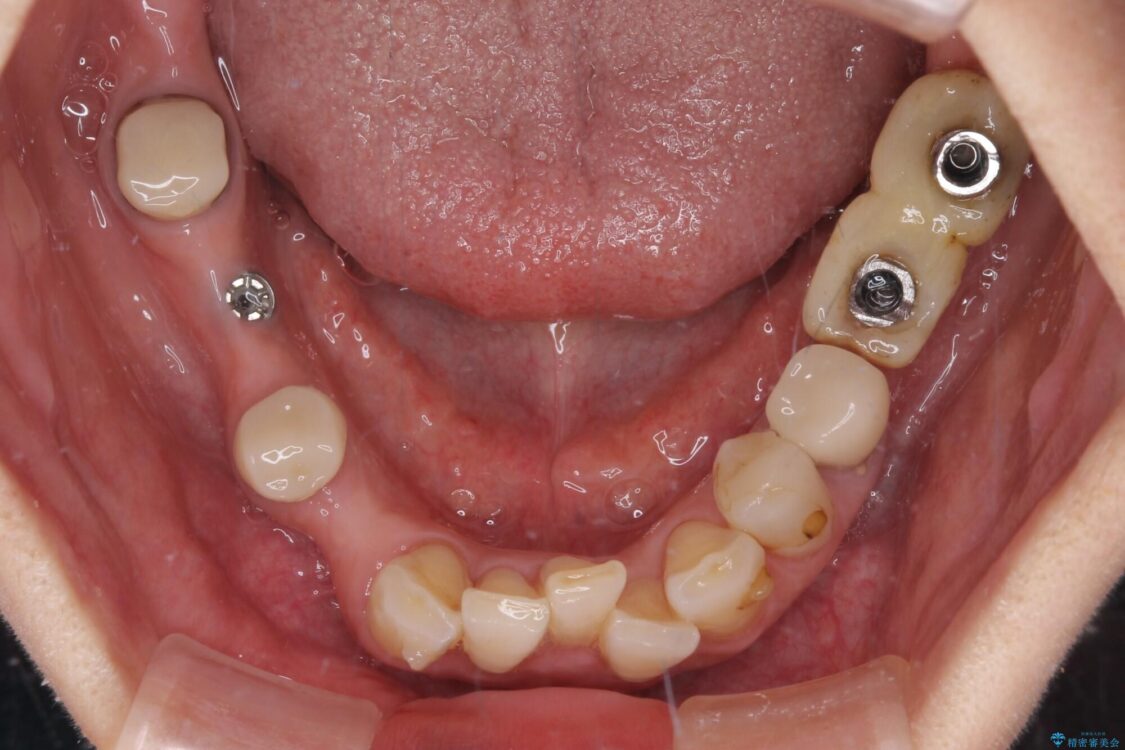

ご主人が当院に通院されていたことで、ご紹介により来院されました。 以前通院していた医院で、奥歯のインプラント埋入、前歯部のインビザライン矯正を行ったものの、そのまま放置してしまったとのことで来院された患者様です。

下顎前歯や上顎奥歯などをワイヤー装置により部分矯正を行い、歯列を整えた上でインプラント部分を含めてオールセラミッククラウンにて補綴治療を行うこととしました。

インプラント上の仮歯がボロボロになり、前歯に非常に負担のかかる状態であったため、早急に奥歯の仮歯を修復し、矯正治療、奥歯の補綴治療、前歯の補綴治療と順々に進めて行きました。

治療前

• 放置したインプラントとインビザライン 全顎リカバリー治療 治療前画像